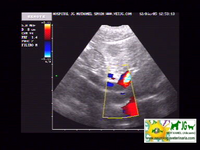

ecografía donde se aprecian las neoplasias hepáticas |

intentamos buscar el shunt portosistémico, pero no es visible ni con el doppler |

Se aprecia la vena porta muy aumentada de tamaño y sinuosa, por lo que es previsible que haya shunts, aunque no los distingamos |